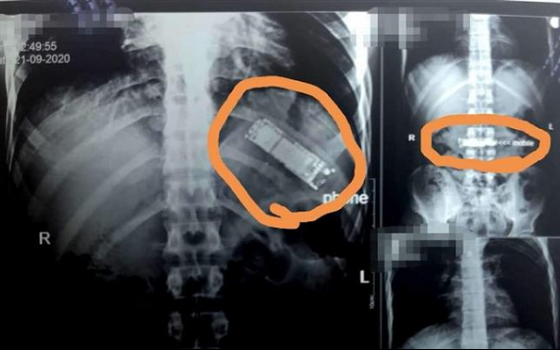

أحداث اليوم - شهدت إحدى مستشفيات مصر واقعة غريبة من نوعها، بعدما تمكن الأطباء من استخراج هاتف محمول من معدة مريض ابتلعه منذ ستة أشهر.

وبحسب ما نشرته وسائل محلية مصرية، بينها صحيفة الشروق، فقد ذهب مريض إلى مستشفى أسوان الجامعي، حيث كان يعاني آلاما شديدة في البطن. وبعدما أجريت له أشعة وفحوصات طبية، تبين وجود التهابات شديدة في البطن والأمعاء.

وتقول الصحيفة إن طاقم الجراحة بمستشفى أسوان أجروا عملية جراحية للرجل، و"نجحوا فى استخراج جسم غريب من معدته، وتبين أنه هاتف محمول".

ونقلت عن الدكتور محمد زكي الدهشوري عميد كلية الطب ورئيس مجلس إدارة مستشفيات جامعة أسوان قوله إنها الواقعة الأولى من نوعها التي يقوم فيها مريض بمستشفى أسوان بابتلاع هاتف محمول.

وأضاف أن الهاتف ظل فى معدة المريض منذ 6 أشهر، مما أدى إلى حجب الطعام.